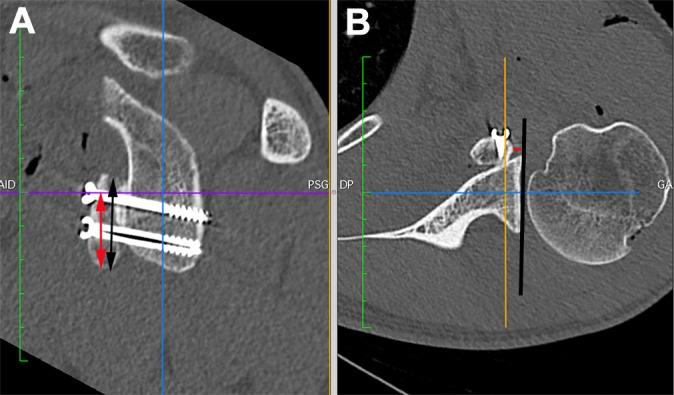

A total of 49 patients who underwent a Latarjet procedure for the treatment of recurrent anterior shoulder instability were prospectively included; the procedure was performed with the freehand technique in 22 patients (group 1) and with use of a parallel drill guide during screw placement in 27 patients (group 2). All patients underwent a postoperative computed tomography scan with the same established protocol. The scans were used to evaluate and compare the position of the CG in the sagittal and axial planes, the direction of the screws (α angle), and overall contact of the graft with the anterior surface of the glenoid after the 2 surgical techniques.

The CG was placed >60% below the native glenoid equator in 23 patients (85.2%) in group 2, compared with 14 patients (63.6%) in group 1 ( = .004). In the axial plane, the position of the CG in group 2 patients was more accurate (85.2% and 88.9% flush) at the inferior and middle quartiles of the glenoid surface ( = .012 and .009), respectively. Moreover, with the freehand technique (group 1), the graft was in a more lateral position in the inferior and middle quartiles ( = .012 and .009, respectively). No differences were found between groups 1 and 2 regarding the mean α angle of the superior (9° ± 4.14° vs 11° ± 6.3°, = .232) and inferior (9.5° ± 6° vs 10° ± 7.5°, = .629) screws. However, the mean contact angle (angle between the posterior coracoid and the anterior glenoid surface) with the freehand technique (3.8° ± 6.8°) was better than that of the guide (8.55° ± 8°) ( = .05).

Compared with the classic freehand operative technique, the parallel drill guide can ensure more accurate placement of the CG in the axial and sagittal planes, although with inferior bone contact.

前瞻性纳入49例行Latarjet手术治疗复发性前肩关节不稳的患者;22例患者采用徒手技术进行手术(第1组),27例患者在螺钉置入时使用平行钻导向器(第2组)。所有患者均按照相同的既定方案进行术后计算机断层扫描。扫描用于评估和比较两种手术技术后CG在矢状面和轴平面上的位置、螺钉方向(α角)以及移植骨与肩胛盂前表面的整体接触情况。

第2组23例患者(85.2%)的CG放置在天然肩胛盂赤道下方>60%,而第1组为14例患者(63.6%)(P = 0.004)。在轴平面上,第2组患者的CG在肩胛盂表面下四分位和中四分位的位置更准确(分别为85.2%和88.9%平齐)(P = 0.012和0.009)。此外,采用徒手技术(第1组)时,移植骨在下四分位和中四分位处于更外侧的位置(分别为P = 0.012和0.009)。第1组和第2组在上部螺钉(9°±4.14°对11°±6.3°,P = 0.232)和下部螺钉(9.5°±6°对10°±7.5°,P = 0.629)的平均α角方面未发现差异。然而,徒手技术的平均接触角(喙突后部与肩胛盂前表面之间的角度)(3.8°±6.8°)优于导向器的平均接触角(8.55°±8°)(P = 0.05)。

与传统的徒手手术技术相比,平行钻导向器可确保CG在轴平面和矢状面上更精确的放置,尽管骨接触较差。